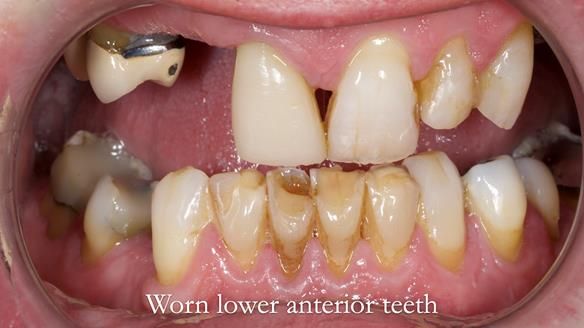

- Bruxism: The upper and lower teeth are worn and chipped due to heavy clenching and grinding. With a powerful bite and limited space for replacement teeth, dental implants supported fixed teeth are not recommended. A simpler solution is a metal-based partial denture/splint (“Combat denture”) as planned below. This will act as a splint to protect and replace the missing teeth.

- Lower Front Teeth: These can be restored to improve their appearance and protect them from further wear. I recommend this treatment but it’s optional and would be done after fitting the upper denture.

Treatment Process: I provided the clinical work, while Rowan Garstang handled the technical work. The treatment required five visits to fit the RPD. The worn lower anterior teeth were then built up. Unfortunately, I did not check the guidance on the denture teeth after this, and tooth 11 fractured off the denture. Brian was very understanding, and I adjusted the denture thoroughly. It has been fracture-resistant and trouble-free for the last three years.